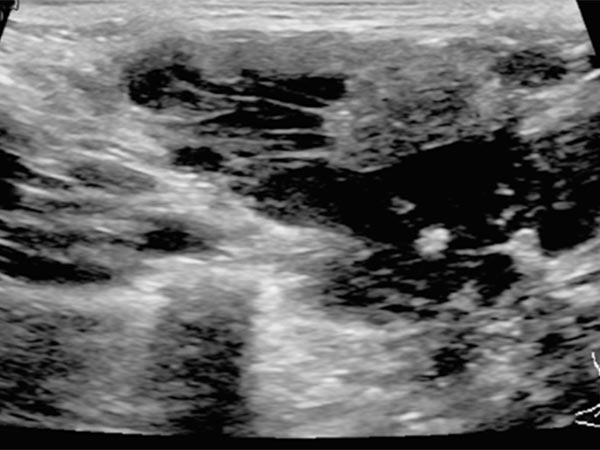

B-scan ultrasonography (longitudinal section) shows the venous malformation to be relatively homogeneously hypoechoic to anechoic. The venous dysplastic vascular channels are compressible with the ultrasound transducer and contain liquid blood.

B-scan ultrasonography (cross-section) also shows the venous malformation as combined hypoechoic to anechoic. The more echogenic parts correspond to sections of the venous malformation in which the contained blood has already clotted. In the anechoic portions, the contained blood is still liquid. In addition, a small phlebolith is found in the lesion, which is practically pathognomonic for a venous malformation.